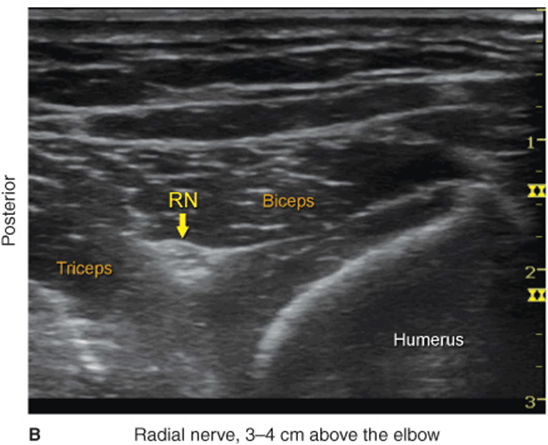

The radial nerve is best visualized above the lateral aspect of the elbow, lying in the fascia between the brachioradialis and the brachialis muscles (Figure 33-2). The transducer is placed transversely on the anterolateral aspect of the distal arm, 3–4 cm above the elbow crease (Figure 33-1A). The nerve appears as a hyperechoic, triangular, or oval structure with the characteristic stippled appearance of a distal peripheral nerve. The nerve divides just above the elbow crease into superficial (sensory) and deep (motor) branches. These smaller divisions of the radial nerve are more challenging to identify in the forearm; therefore, a single injection above the elbow is favored because it ensures blockade of both. The transducer can be slid up and down the axis of the arm to better appreciate the nerve within the musculature surrounding it. As the transducer is moved proximally, the nerve will be seen to travel posteriorly and closer to the humerus, to lie deep to the triceps muscles in the spiral groove (Figure 33-3).

FIGURE 33-2. (A) Radial nerve anatomy at the distal third of the humerus. (B) Sonoanatomy of the radial nerve at the distal humerus. Radial nerve (RN) is shown between the biceps and triceps muscles at a depth of approximately 2 cm.